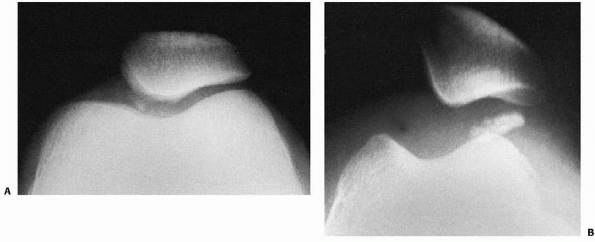

are more common than once thought. They are typically associated with

acute lateral patellar dislocations. The most common locations for

these fractures are the medial patellar facet or the lateral femoral

condyle (Fig. 24-13). The osteochondral

fracture fragments may range from small incidental loose bodies to

large portions of the entire articular surface. The prevalence of

osteochondral fractures associated with acute patella dislocation

ranges from 25% to 50%.13,43,95,206,229,282 Matelic et al.206 found 67% of children presenting with an acute hemarthrosis of the knee had an osteochondral fracture.

FIGURE 24-13 Osteochondral fractures associated with dislocation of the right patella. A. Medial facet. B. Lateral femoral condyle.

but the rest of the quadriceps muscle-patellar ligament complex

continues to apply significant compression forces as the patella

dislocates laterally. These forces are believed to cause fracture of

the medial patellar facet, the lateral femoral condyle articular rim,

or both (see Fig. 24-13).160,234,254